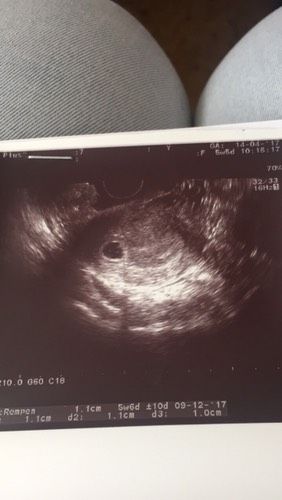

Ну все)) сегодня сходила на узи! Нашли мою горошинку там где положено (то есть в матке). Сказали через пару недель прийти сердечко послушать. Пы.сы: вот так вот, как после этого в чудо не верить? Три года ждали. Собирались на эко уже, начали анализы сдавать, даже на овулю забила, а тут такой сюрприз.

Фото увидела сейчас и вспомнила когда с мужем пошли на 1узи с первой б, когда ему показали он такое удивленное лицо сделал и говорит эта горошина и есть мои ребенок? А где руки ноги? голова где? Потом молчание сек 5 и тут выдал "на меня похож"мы с доктором долго смеялись над этими словами. Здоровья вам легкой беременности и легких родов.